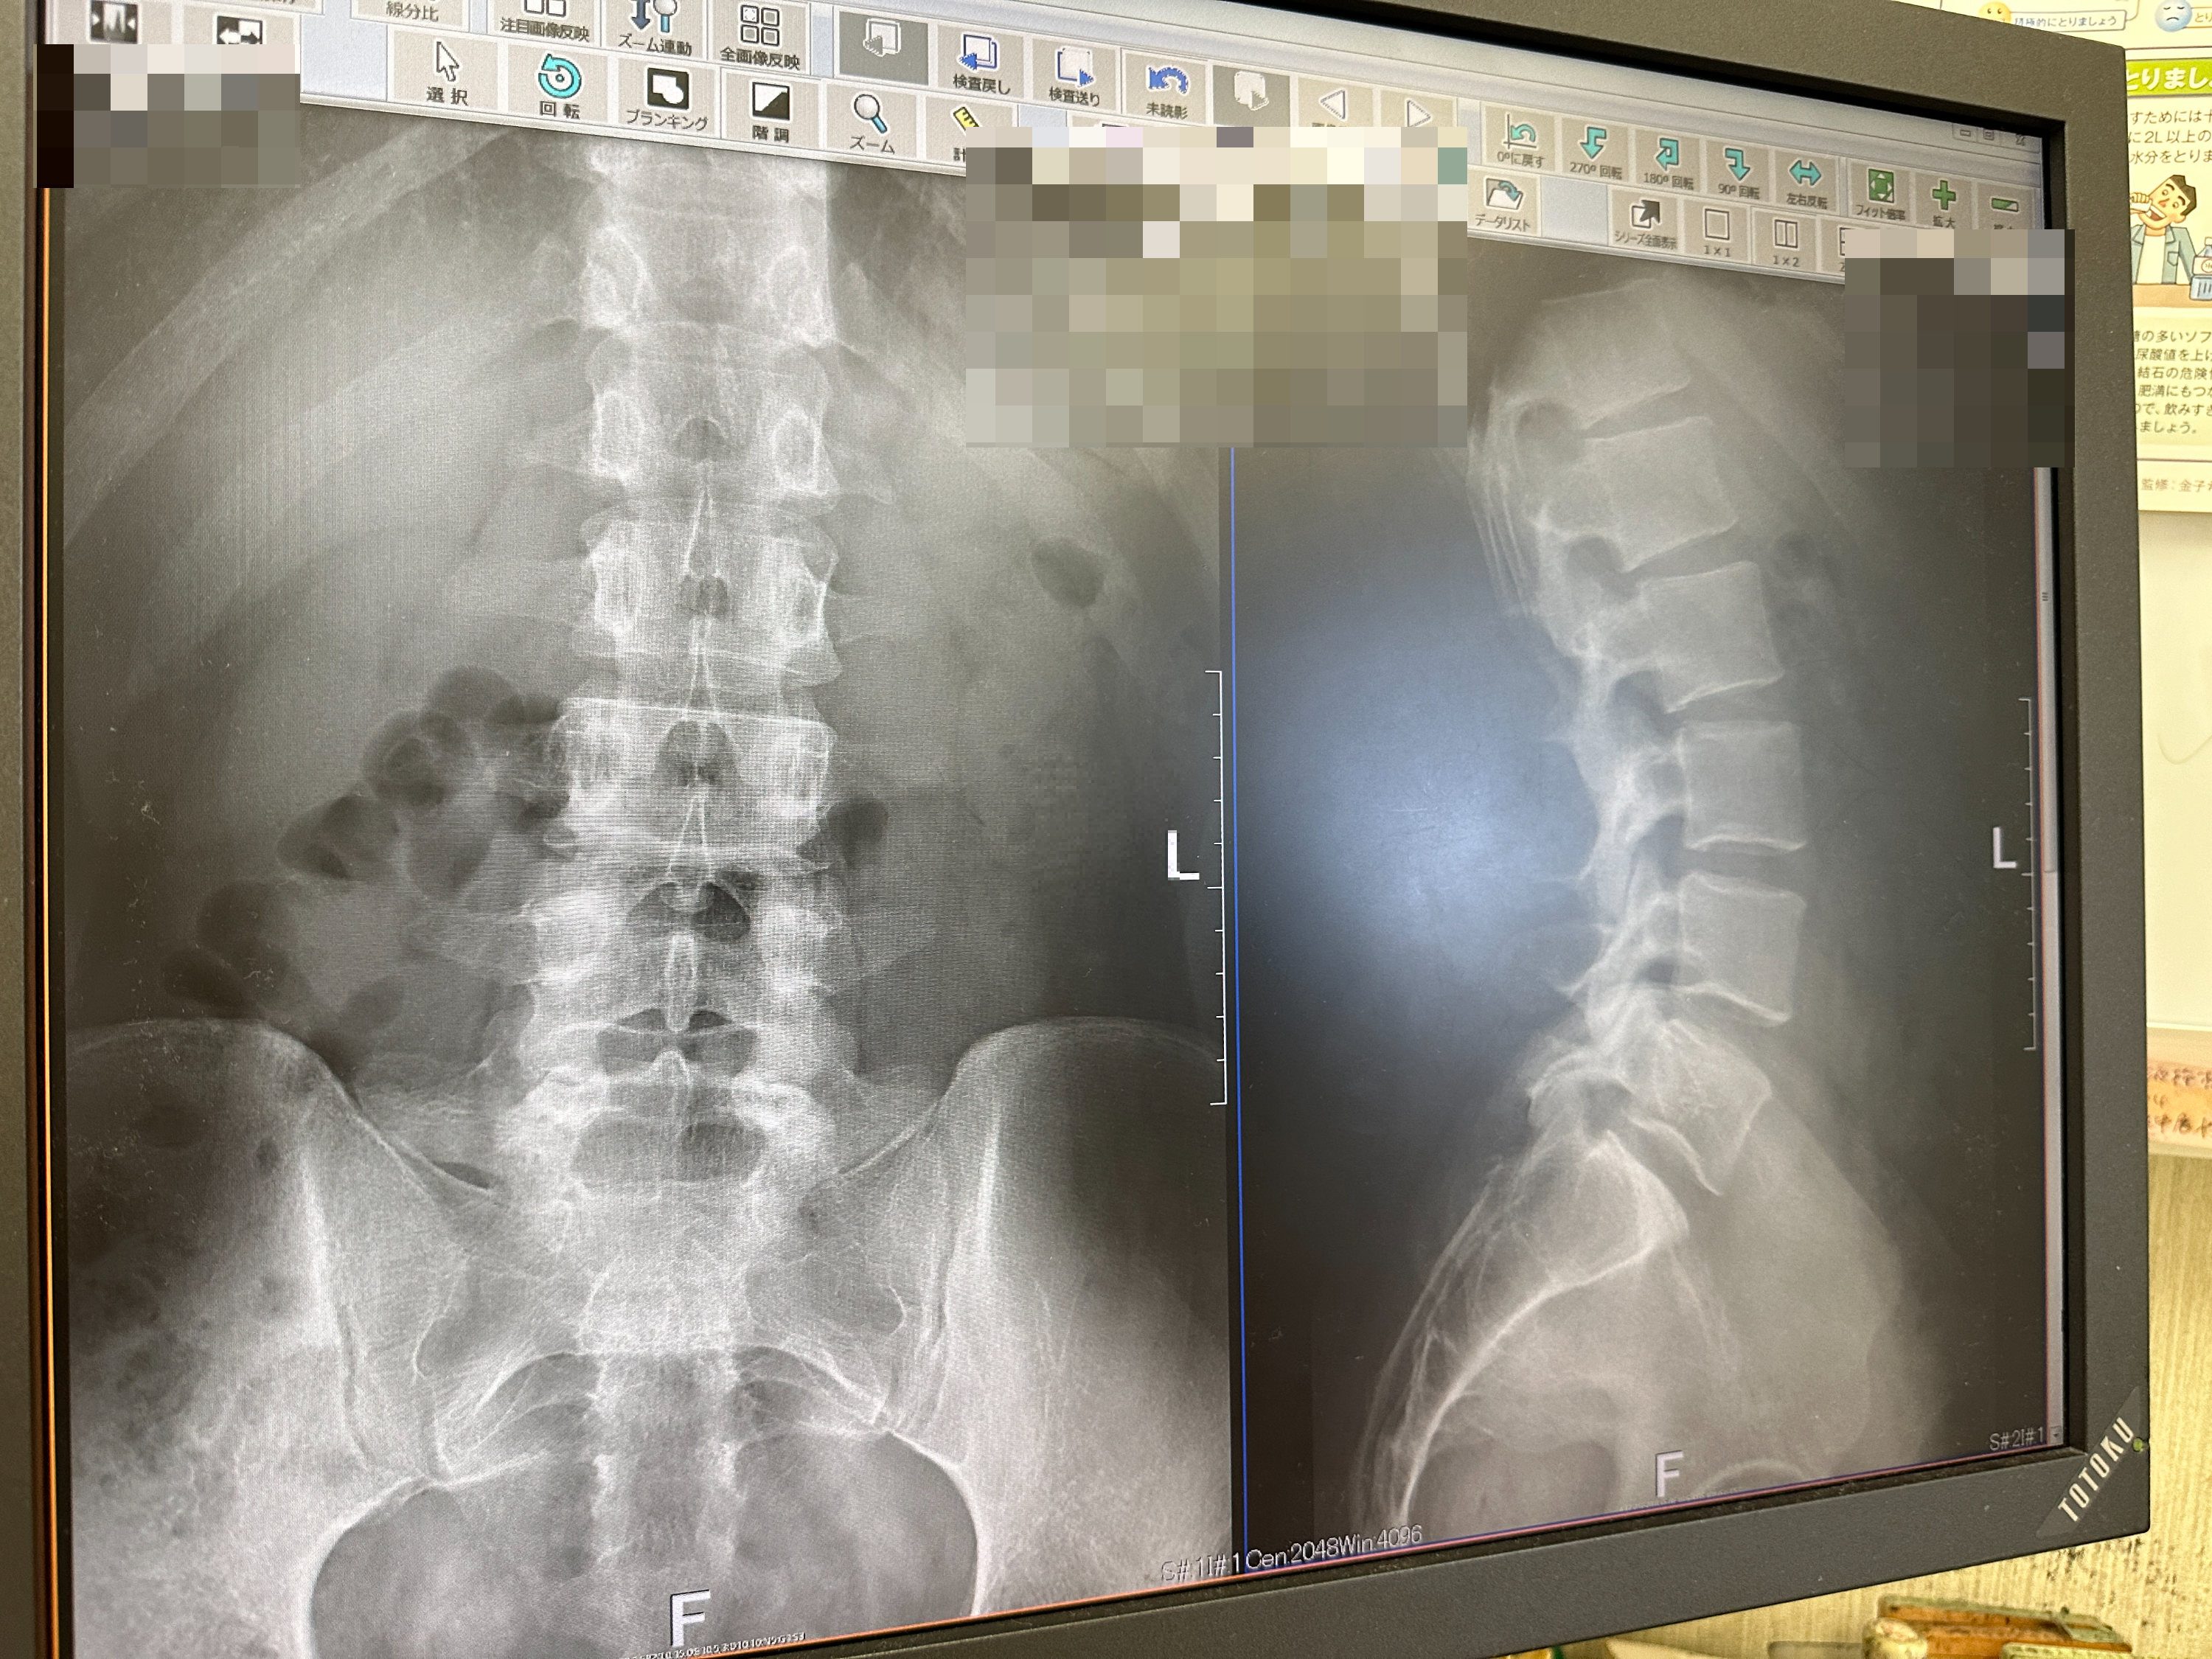

그리고 일본에서 처음으로 병원도 갔다.

헬스를 하다가 무리해서 허리를 다쳤었다.

그냥 시간이 지나면 나을 줄 알았는데 상태가 전혀 호전되지 않아서 정형외과를 방문한 것이다.

혹시나 디스크가 터진 게 아닐까 걱정도 많이 했는데 다행히도 최악의 상황은 아니었다.

다행히 병원에서 처방해 준 약과 파스 덕분에 허리는 많이 호전되었다.